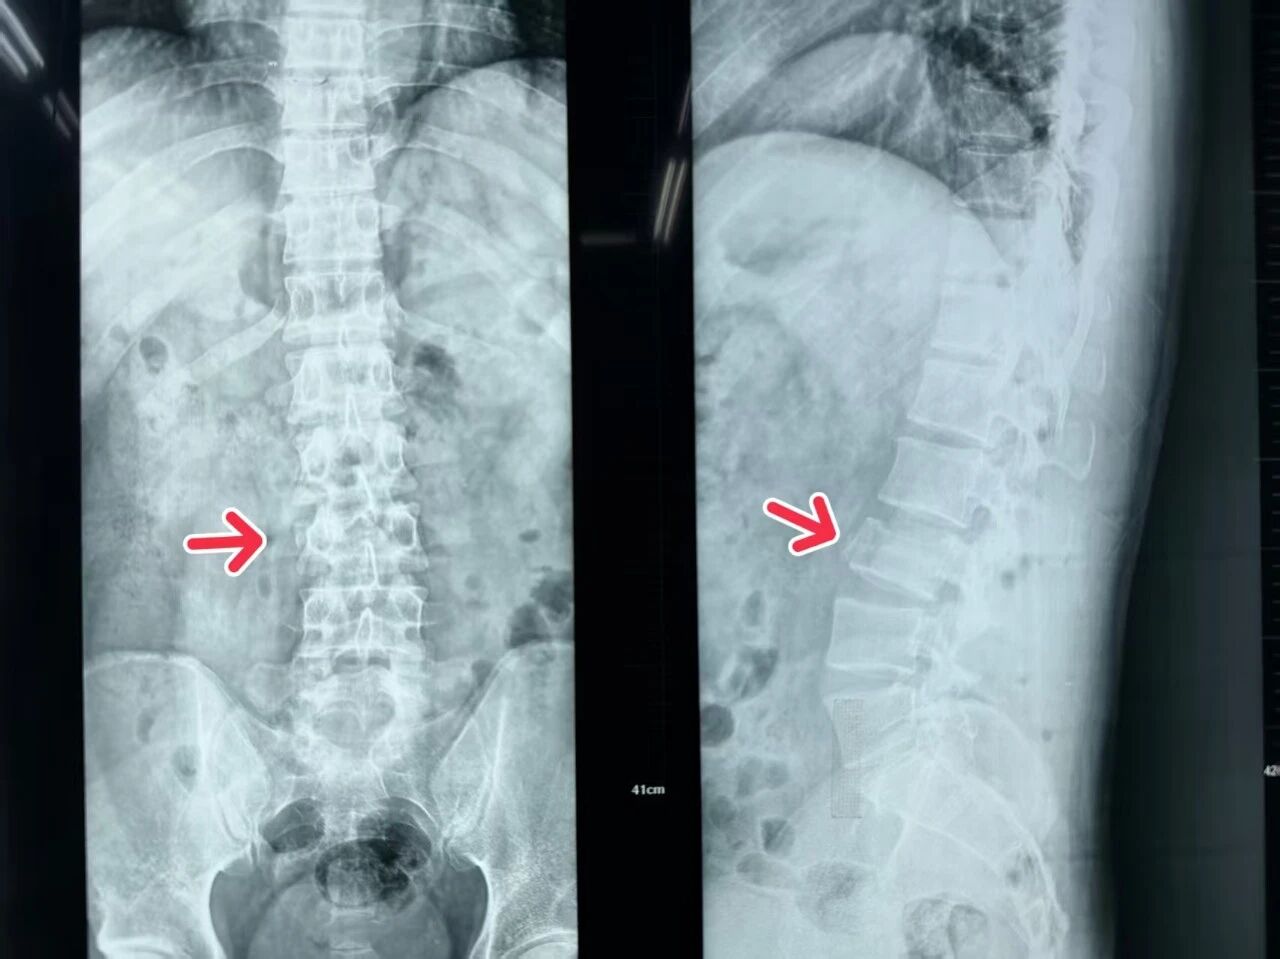

在姬主任的带领下,手术团队为患者施行了“腰椎骨折切开复位内固定+椎管减压术”。手术通过小切口精准操作,有效解除了骨折对脊髓神经的压迫,并实现了骨折椎体的复位与稳定固定。整个手术过程顺利,患者生命体征平稳,术后患者神经刺激症状显著缓解,安返病房。

医疗团队为患者制定了周密的治疗与康复计划,包括脱水消肿、营养神经、预防感染及早期康复训练等,并密切监测其神经功能恢复情况。在医护人员的精心照护下,患者恢复良好,四肢感觉与运动功能正在逐步改善。患者内心充满感激,他由衷感谢姬主任团队精湛的医术与无私的奉献,并表示将积极配合康复,争取早日重返社会,用实际行动回馈这份生命的馈赠。